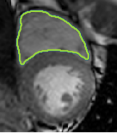

4.2 Visual assessment

We select the case that achieves the highest and lowest dice score for visual assessment. Fig. 4 shows example segmentation results where the proposed method achieved the highest agreement with the ground truth delineations. Fig. 5 shows example segmentation results where the proposed method achieved the lowest agreement with the ground truth delineations.

| (a) LV BG | (b) RV BG | (c) LV NM | (d) LV ME | (e) LV MS |